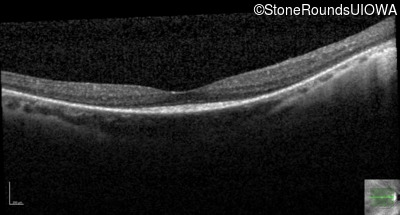

Optical Coherence Tomography - Left - 20/20 -2

Exemplar / OCT Stack

OCT Stack